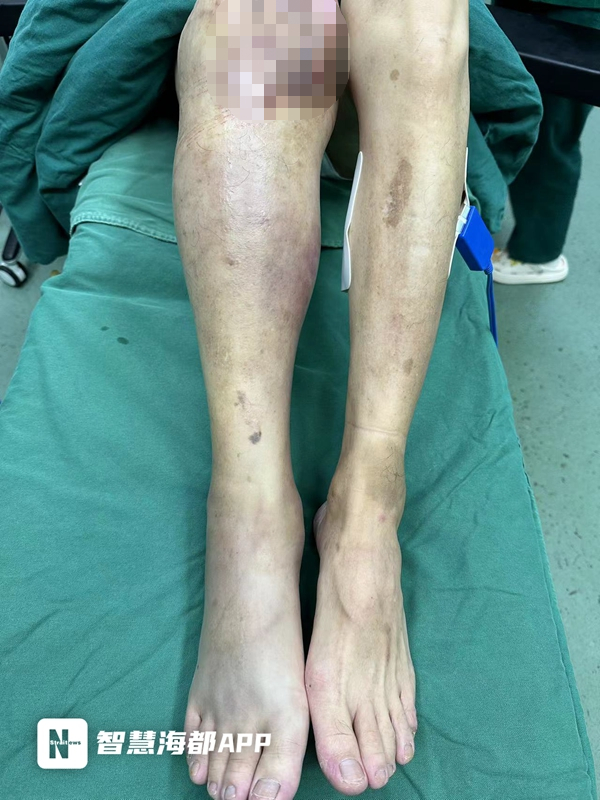

小张是一位外来务工者。8月中旬的一天,他吃了生腌海鲜,还喝了点酒,回去时摔了一跤右腿磕破,他没在意。不料第二天他就发起高烧,右足背到右大腿红肿,皮肤发黑。撑到第三天,他被同事送医。

“人送来时,高烧39.5℃,精神萎靡,血压低,出现脓毒性休克、多脏器功能不全;从右足背到右大腿肿胀明显,皮肤发乌,局部出现血疱,肢体冰凉,右下肢广泛缺血性坏死。”接诊的烧伤创面修复科主治医师魏智艺立即给予补液抗休克、抗感染、脏器功能维护等一系列治疗,并对右下肢进行抢救性手术。

由于心脏、肝脏以及肾脏等脏器功能受损,小张还需进行血透、生命支持等治疗,术后被送入ICU进一步救治。